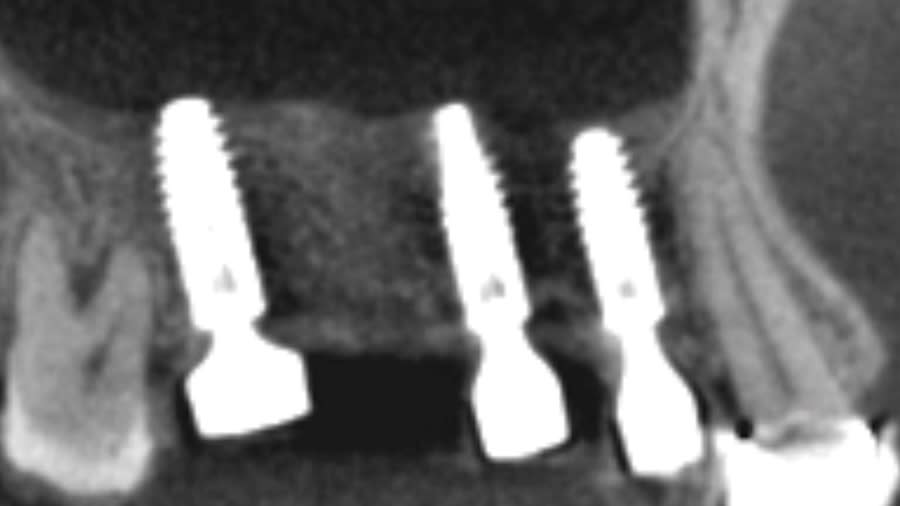

Case 1 (Figure 3 through Figure 24) depicts a 3-year follow-up of combined osseodensification sinus protocol IV in a severely resorbed maxillary ridge with ≤0.5 mm bone height in molar sites and horizontal deficiency at the first premolar site, using a two-stage approach for implant placement.